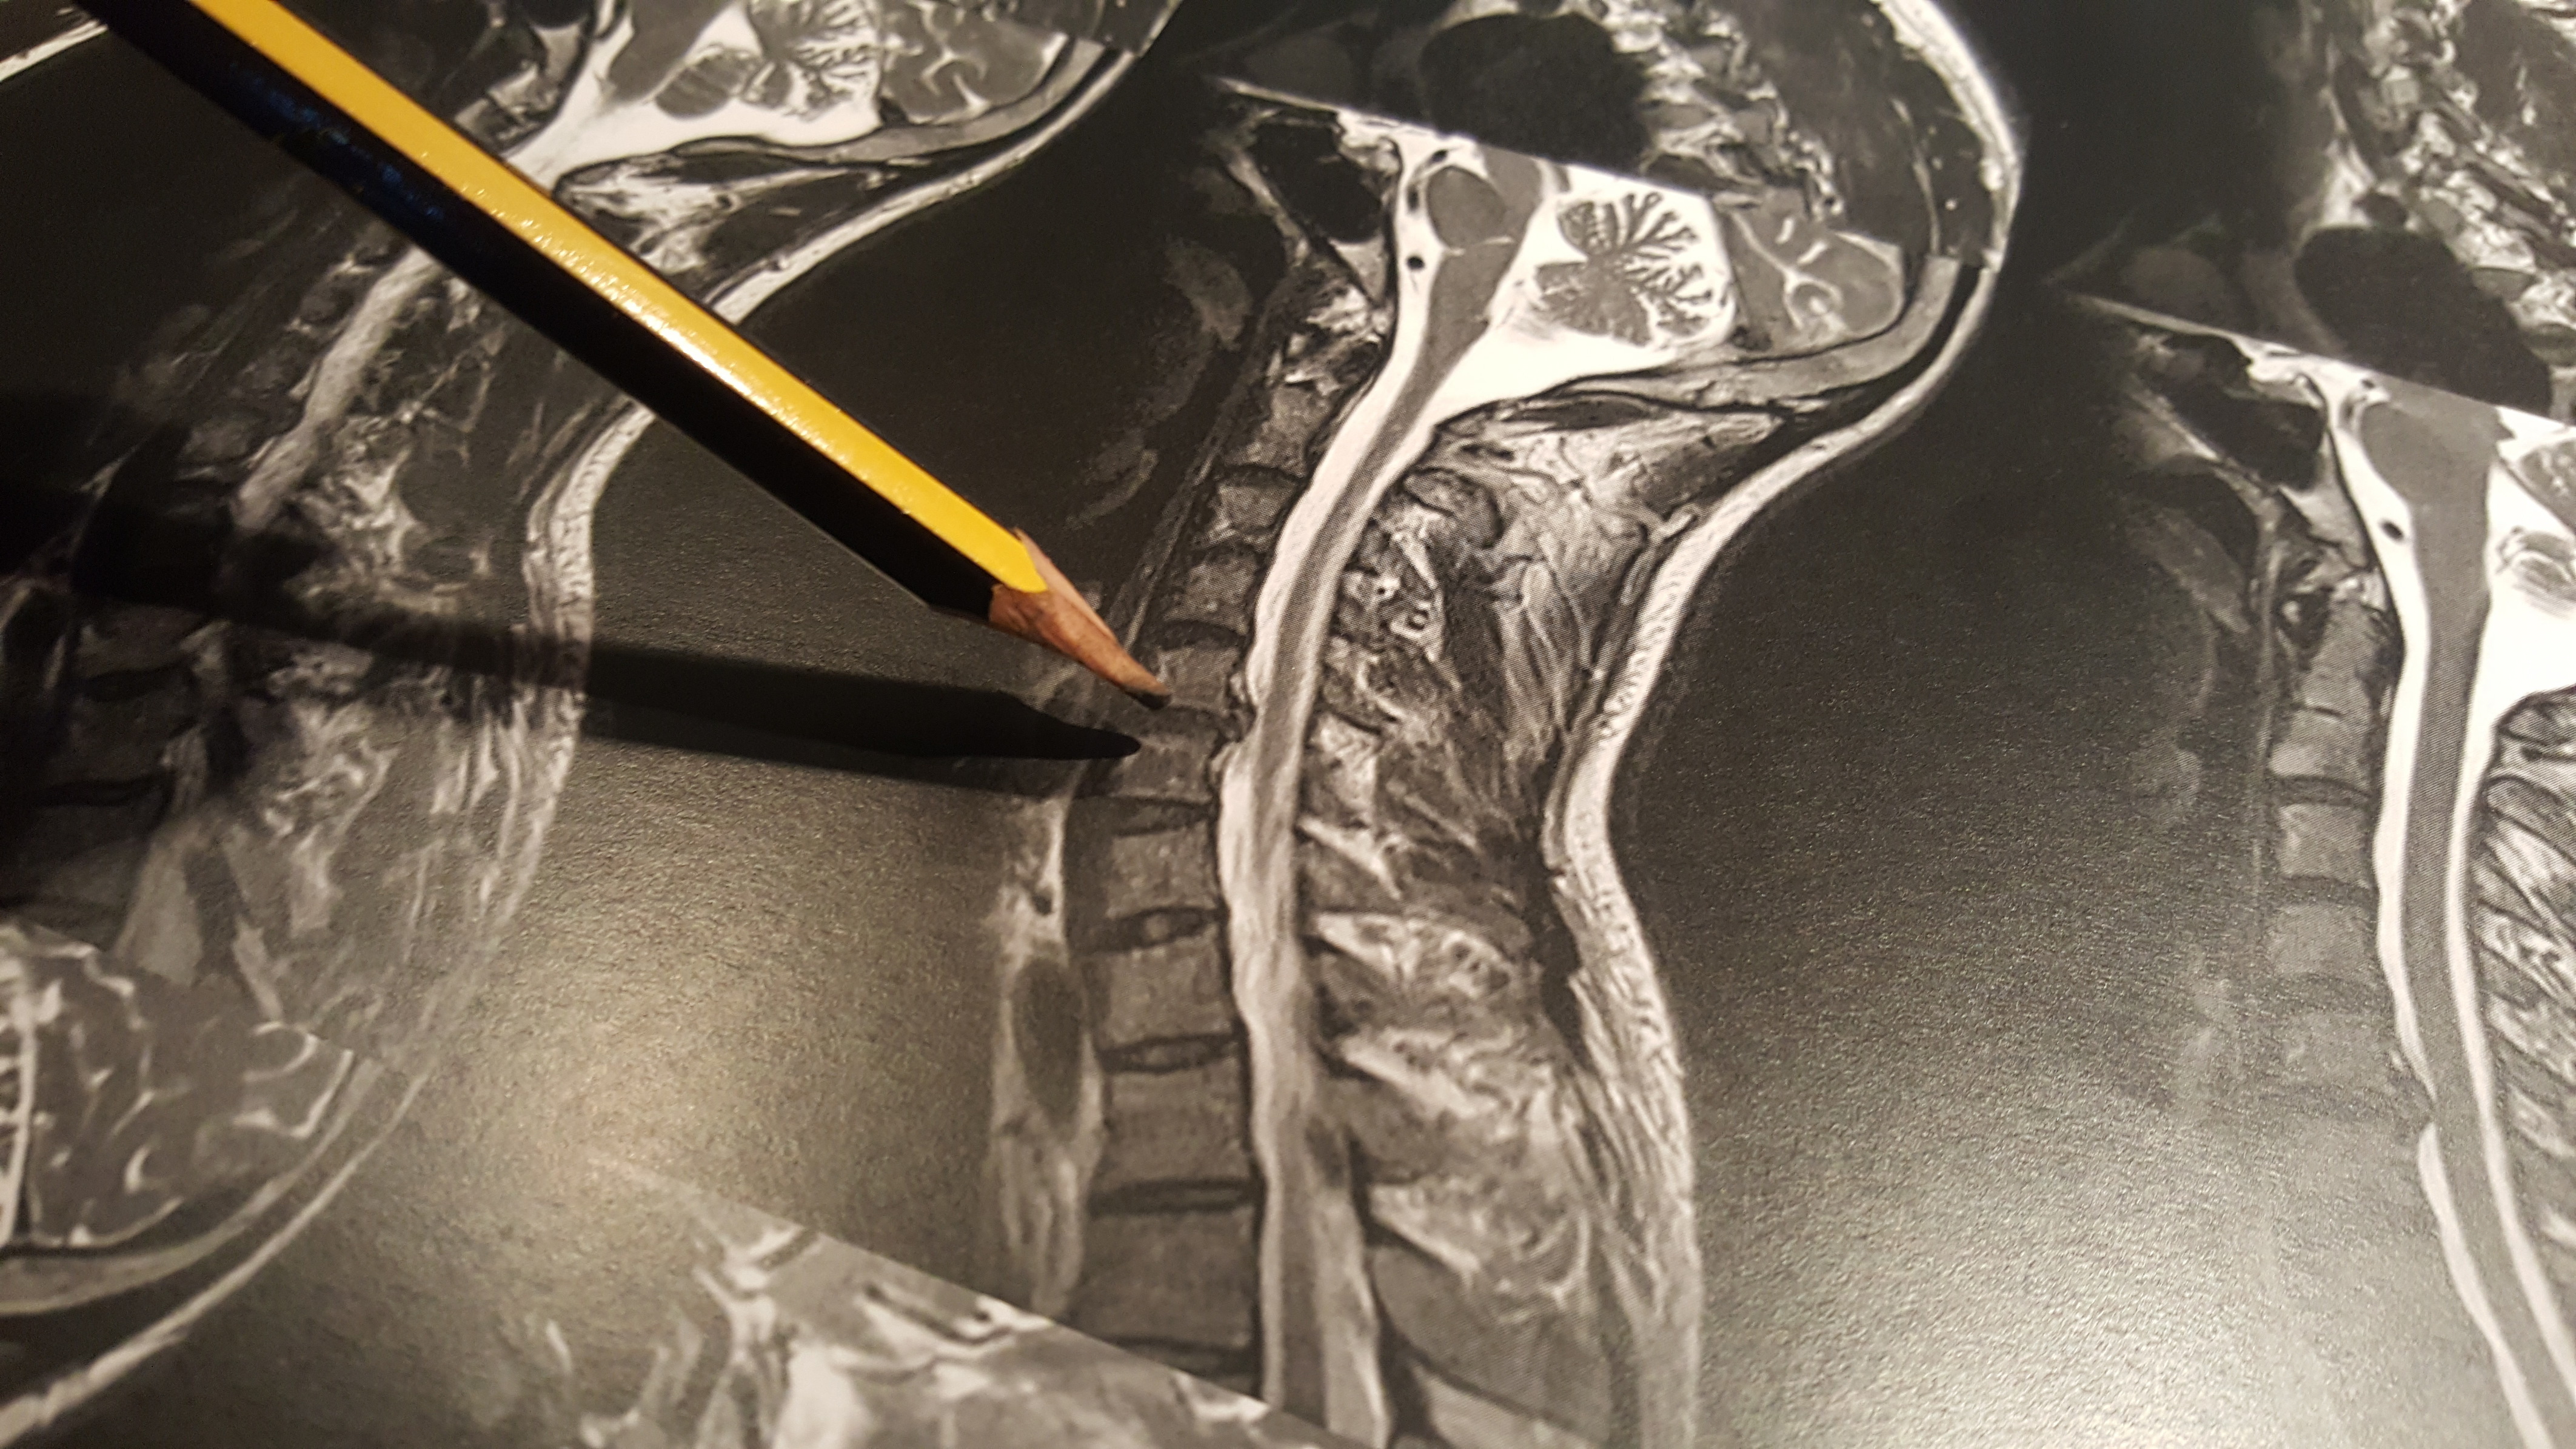

Cervical Disc Prolapse

A disc prolapsed is often referred to as a slipped disc, however please do not worry as your disc cannot “slip” anywhere. Think of your discs as shock absorbers between the vertebrae of your spine. What actually occurs, is the thick gel-like nucleus in the middle of the disc bulges out through a tiny fault in the fibrous disc wall. This small bulge of nucleus can therefore irritate and compress the nerve root causing pain, which may radiate down the leg. There are different types and severities of disc prolapse, which can be seen in the diagram below.